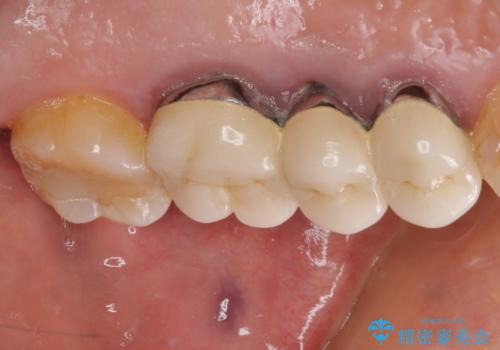

抜歯後、骨吸収量が多く、歯肉のラインが不揃いとなっているため骨造成術を、硬い歯肉が失われて清掃性が低下するため角化歯肉の移植術を行い、また並行して支台歯の根管治療を行っていき、環境を整えた上でオールセラミックブリッジにて補綴治療を行うこととしました。

インプラントによる補綴治療も検討しましたが、骨吸収量が多いこと、後方の支台歯が今後抜歯となる可能性が否定できないことを鑑み、将来抜歯となった際にインプラント2本を埋入することで患者様と事前にお話をしました。